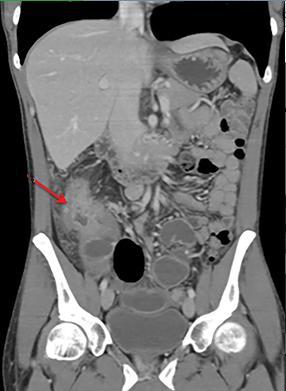

Aspect TDM du tuberculose ileocaecale est : Epaissisement

circumferentiel de la paroi ileum et caecum . Asymetrique

epaissisement de la valve ileocaecale .Mesenteric

lymphadenopathie et tuberculose pulmonaire est le plus

souvent .

Tuberculose ileo-caecale :

Image de epaissisement circumferentiele hyperdense

de ceacum avec lymphadenopathie mesenterique (

fleche rouge ). Image

TDM en coupe coronale |